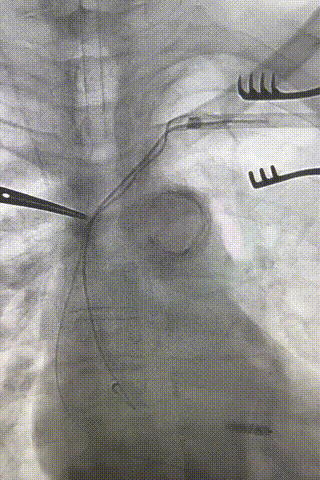

心房电极拔除:上腔静脉造影显示锁骨下静脉、无名静脉及上腔静脉完全闭塞,心房电极与锁骨下静脉粘连非常严重,激光鞘逐步消蚀并与外鞘交替使用缓慢前行,使用超硬泥鳅导丝辅助松解粘连组织(图15-18)。耗时1小时成功拔除心房电极,可见长段粘连组织(图19-22)。

图15-18